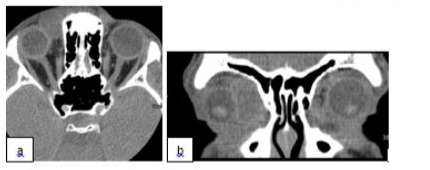

A nineteen-year-old healthy male patient without a significant clinical history, presented with unpainful upper right progressive eyelid swelling increasing in size through several months before hospital admission. On examination his BCVA was 0.8 right eye and 1.0 left eye, full eye movements in all directions, swelling of his right upper eyelid. Optic nerve and neuroophthalmological function were normal. CT scan of orbit was performed at presentation and showed sharply delineated, noncalcified, solid extraconal mass with 2.4 cm of largest tumor diameter located in the medial half of right orbit, with lateral downward displacement of the globe without bone or intracranial invasion (Figure 3).

Figure 3: CT, Axial (a) and Coronal (b) Section, before treatment (description above).